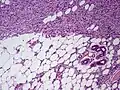

Histopathological image of dermatofibrosarcoma protuberans. Local recurrence long after the first excision. H&E stain